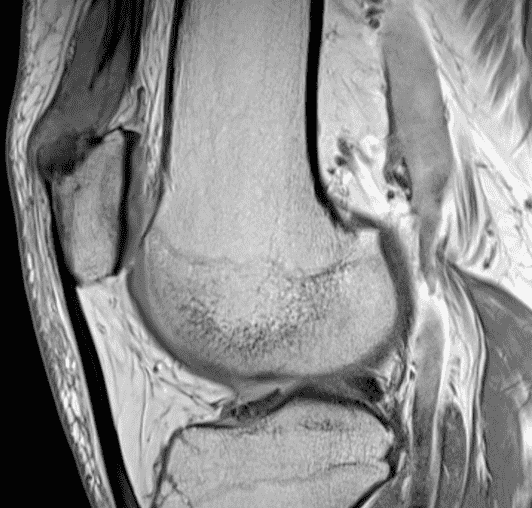

A 65 year-old-man presents with a palpable mass in the anterior knee and generalized pain. Sagittal (1A) fat-suppressed T2-weighted and (1B) proton density-weighted images are shown. What are your findings? What is your diagnosis?

Figure 2: An ill-defined, infiltrative mass superficial to and involving most of the distal quadriceps tendon (red arrows) has intermediate signal on the fat-suppressed fluid-sensitive (2A) and proton density-weighted (2B) images, with faint marrow edema in the adjacent patella (yellow arrow).